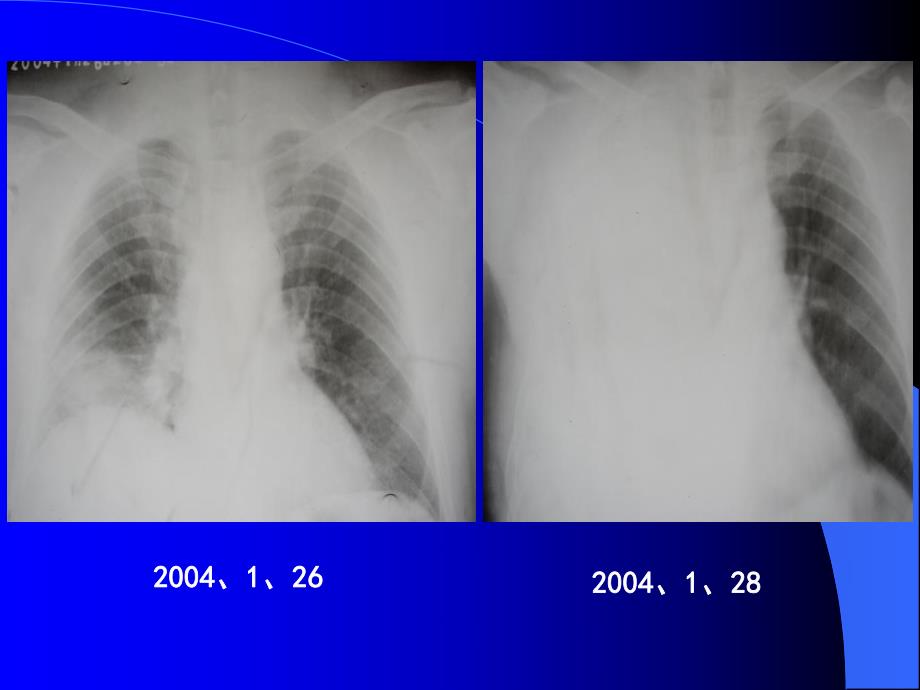

1、社区获得性肺炎的经验治疗社区获得性肺炎的经验治疗20042004、1 1、262620042004、1 1、28281.1.所有的所有的CAPCAP病人中,至少一半的病人无病人中,至少一半的病人无法明确病原菌诊断法明确病原菌诊断2.2.许多诊断检查的结果都需要一定时间许多诊断检查的结果都需要一定时间3.3.经验性选择抗生素,既能降低肺炎患经验性选择抗生素,既能降低肺炎患者的病死率,又能缩短患者的门诊治者的病死率,又能缩短患者的门诊治疗或住院治疗时间,降低医疗费用,疗或住院治疗时间,降低医疗费用,有利于有限的医疗资源的合理再分配。有利于有限的医疗资源的合理再分配。q美国最常见致死性感染性疾病之一